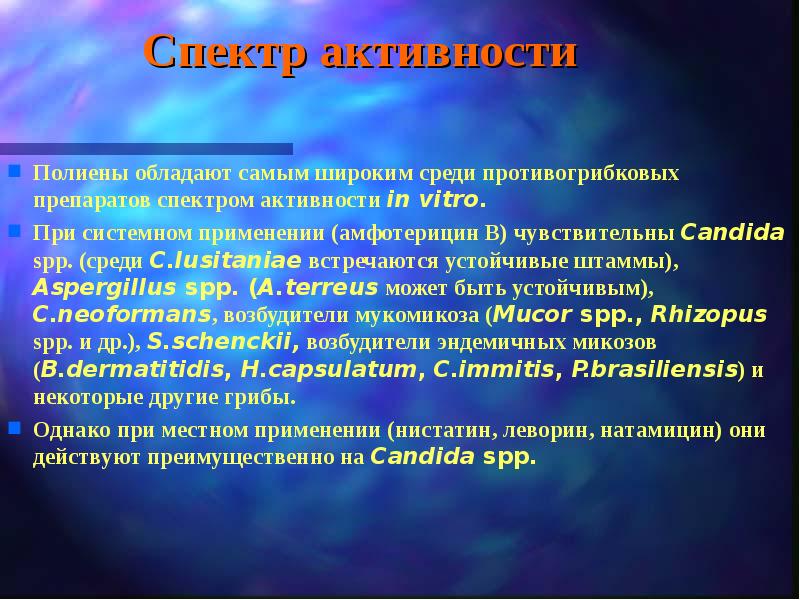

Механизмы действия антимикотиков: схемы и изображения